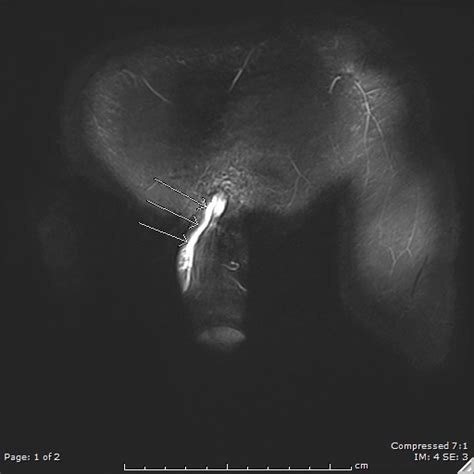

Mondor's disease is a rare condition which involves thrombophlebitis of the superficial veins of the breast and anterior chest wall.

It sometimes occurs in the arm or penis.